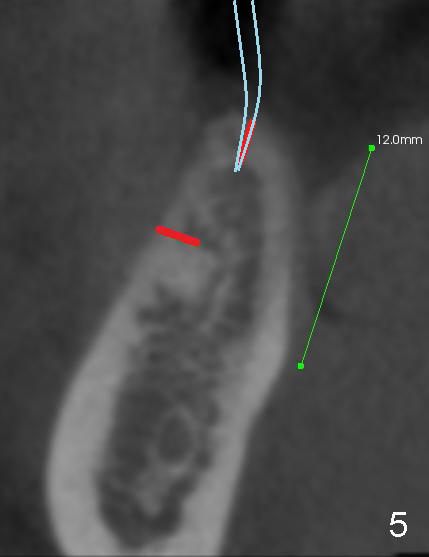

The patient is scheduled to return for implant placement 3 weeks later. The red lines in Fig.4 (CT coronal section) represent bony cuts in the ridge. A transverse incision is made over the top of the ridge with minimal exposure of the ridge. A curved osteotome is inserted into the upper bony cut (Fig.5). As the chisel is tapped in, the buccal segment moves buccally (Fig.6 pink arrow). When the chisel is withdrawn, a pilot drill is used to initiate osteotomy (Fig.7). As drills increase in diameter, the buccal segment continues moving buccally (Fig.8). Finally a bone-level implant (4.1 or 4.5x12 mm, Fig.9) or sub-crestal implant (4 or 4.5x8) is placed. Will the ridge split work?